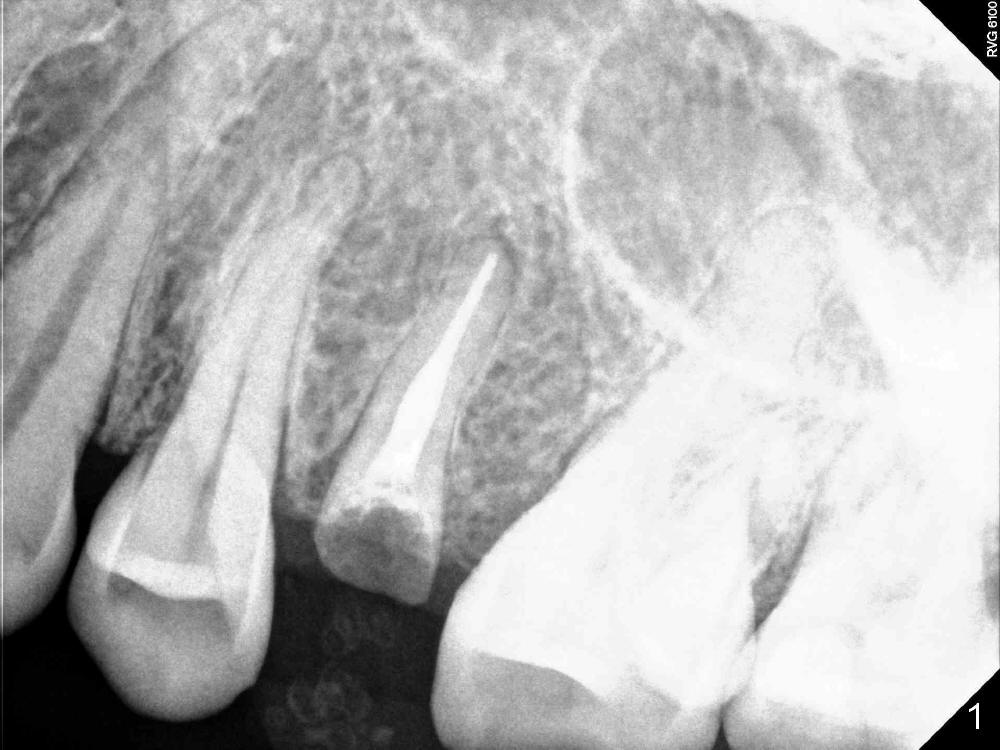

This is today's case; female, 54yrs,coming with broken tooth, I done it 12yrs ago.immediate implant #13 with healing abutment, It took me 40 minuses to dig out the fractured root. The bone spoon You brought to me is very helpful. Thanks!

You are welcome.  There should not be a lot of granulation tissue to be removed in this case.  It is one way to use a large implant to achieve primary stability.  The other way is to use a long implant to engage into new bone.

In fact, a 3.8x8 mm DIO implant is exfoliated. Small implants (3.8 mm in diameter) do not have aggressive threads to achieve primary stability, even though the wrench indicates.  In this case, the healing abutment may contribute to failure.  Additionally, the patient's oral hygiene is not so good.   Do you have any good idea how to fix this case?  Thanks.